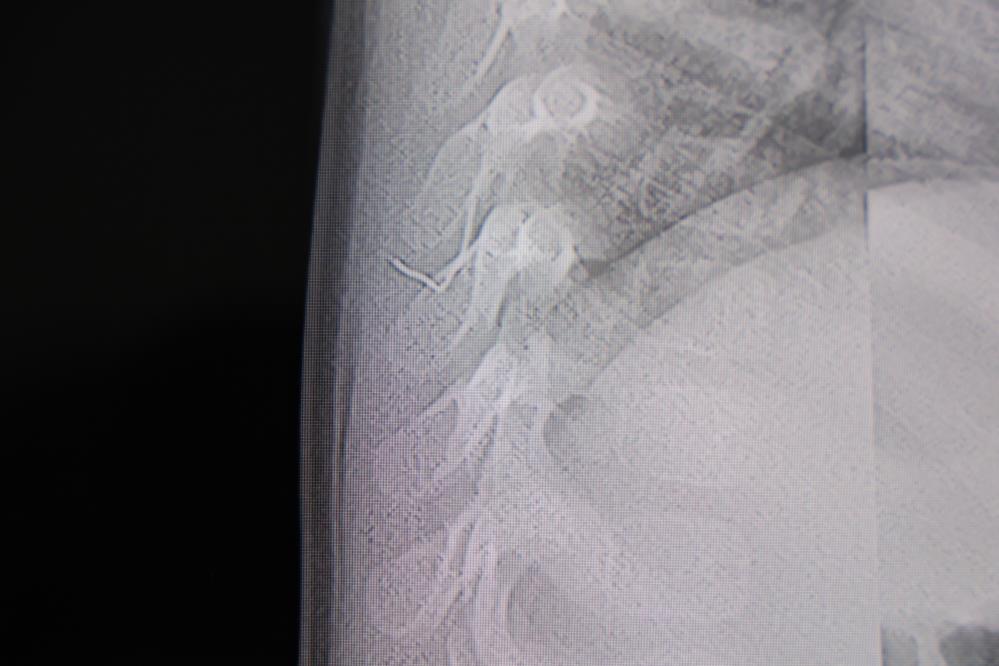

Alınan bilgiye göre, Kahramanmaraş'ta farklı ortopedi, çocuk cerrahisi ve beyin cerrahisi kliniklerine başvurusu yapılan bir yaşındaki bebeğin, sırt bölgesinde yabancı bir cisim olduğu ancak müdahalenin zor olduğu ve 8 yaşına kadar beklenmesi gerektiği bildirildi. Aile, bebekleri için son olarak HG Hospital'e başvurdu. HG Hospital Beyin ve Sinir Cerrahisi Uzmanı Prof. Dr. İdris Altun tarafından yapılan tetkiklerde, yabancı cismin cilt altında, omurilik kanalına yakın bir bölgede olduğu ve akciğer zarına doğru ilerlediği belirlendi. Hasta, genel anesteziye alınmadan, lokal anestezi ve sedasyon eşliğinde ameliyata alındı. Yapılan müdahalede yabancı cisim tamamen çıkarıldı. Çıkarılan cismin, ince zımba teline benzer metal bir tel olduğu ve yaklaşık 2 santimetre uzunluğunda bulunduğu tespit edildi. Hasta, aynı gün taburcu edildi.

Konuya ilişkin açıklama yapan Prof. Dr. İdris Altun, "Sırtında yabancı bir cisim olduğu söylenmiş ancak çıkarılamayacağı ve 8 yaşına kadar beklenmesi gerektiği ifade edilmişti. Bize başvurduğunda yaptığımız tetkiklerde, cilt altında, omurilik kanalına çok yakın ve akciğer zarına doğru ilerleyen bir yabancı cisim tespit ettik. Hastamızı tamamen uyutmadan, lokal anestezi ve sedasyon eşliğinde müdahale ederek lezyonu tamamen çıkardık. Çıkardığımız cismin ince zımba teline benzer, yaklaşık 2 santimetre uzunluğunda metal bir tel olduğunu gördük. Bu yabancı cisim alınmasaydı, bölgede enfeksiyon gelişebilirdi. Enfeksiyon sonucu omurilik kanalında ciddi hasarlar oluşabilir, çocuk büyüdükçe cismin hareket etmesine bağlı olarak omurilikte zedelenmeler meydana gelebilirdi. Ayrıca yana doğru ilerleyerek akciğer zarına ve akciğere batma riski vardı. Bu da enfeksiyona ve ilerleyen süreçte tümörle karışabilecek tablolara neden olabilirdi. Şu an hastamız gayet sağlıklı. Gerekli kontrolleri yaptık ve aynı gün taburcu ettik" dedi.